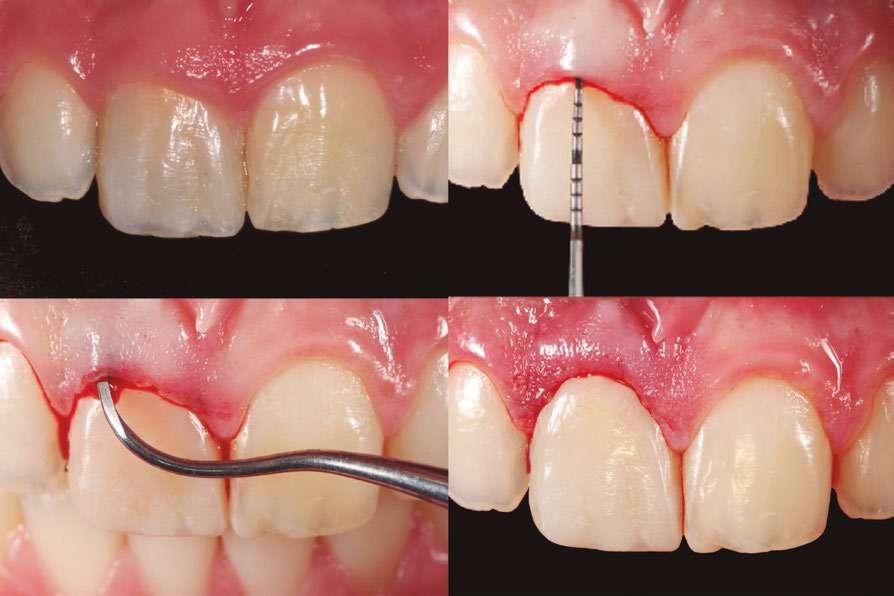

Dada la cercanía a las raíces de los dientes adyacentes y el riesgo de rizólisis de las mismas, se optó por realizar la exodoncia, utilizando para ello anestesia local de la zona (Fig. 2).

Tal y como se puede observar en las imágenes (Fig. 3 y 4) se realizó una incisión sulcular siguiendo el surco gingivodentario lingual sin descargas para despegar un colgajo a espesor total que facilitó un campo quirúrgico suficiente como para poder realizar la ostectomía hasta descubrir la corona del diente (Fig. 5).

La ostectomía se realizó de manera cuidadosa, tanto con el colgajo y las estructuras del suelo de boca, como con los dientes adyacentes y sus raíces. En este caso el diente no requirió odontosección, por lo que su exodoncia pudo ser completada usando un botador recto y unas pinzas adson para su retirada del alveolo (Fig. 6).

Una vez finalizada la intervención se procedió a realizar sutura interpapilar con sutura monofilamento 5/0 (Fig. 7 y 8).

A la paciente se le prescribió una pauta antibiótica postoperatoria de Amoxcilina 500 mg 1/8h durante 5 días, sumada al uso de Ibuprofeno 600 mg con Paracetamol 1g como analgésico de rescate. Fueron pautados enjuagues con clorhexidina 0,2% a partir de las 24 horas de la intervención, revisando la zona a la semana, momento en que se retiró la sutura y se pudo comprobar que la paciente no presentaba ninguna alteración sensitiva en la zona (Fig. 9).